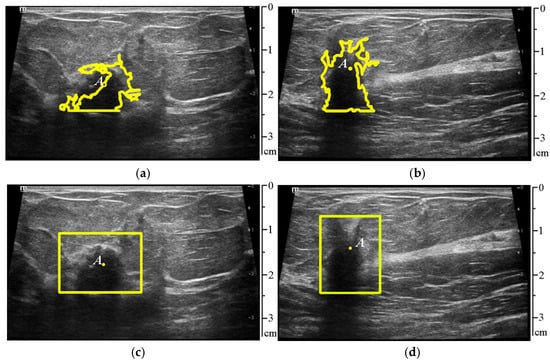

| Metric | Rating of the First Video | Rating of the Second Video | Mean Rating for All 52 Videos |

|---|---|---|---|

| ± | 13.35 ± 12.15 | 17.97 ± 13.99 | 15.37 ± 13.72 |

| IoU | 0.89 | 0.84 | 0.871 |

| TP | 0.88 | 0.86 | 0.875 |

| FP | 0.07 | 0.14 | 0.121 |

| FN | 0.12 | 0.14 | 0.134 |

| Precision | 0.92 | 0.86 | 0.91 |

| Recall | 0.88 | 0.86 | 0.88 |

| F1-score | 0.90 | 0.86 | 0.89 |

| Video Sequence | Metric: ± (Pixels) |

|---|---|

| First video | 12.98 ± 13.15 |

| Second video | 14.18 ± 13.90 |

| Mean for all 52 videos | 13.73 ± 13.189 |